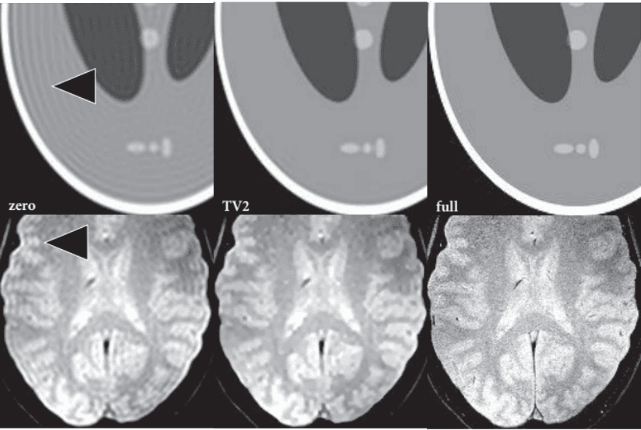

全变分约束外推:对于超出测量部分的K空间数据,利用分段常数对象的简单假设进行推断,利用此方法可以显著减小截断伪影且不影响图像分辨率。

GAN(生成对抗网络):GAN为非监督学习方法之一,由生成网络与判别网络组成,生成网络输出尽可能接近训练集样本,而判别网络的输入为生成网络的输出或真实样本,判别网络要尽可能地分辨出真实样本,两个网络之间相互对抗,通过调节参数,直至判别网络无法辨别出所输入样本的真实性。